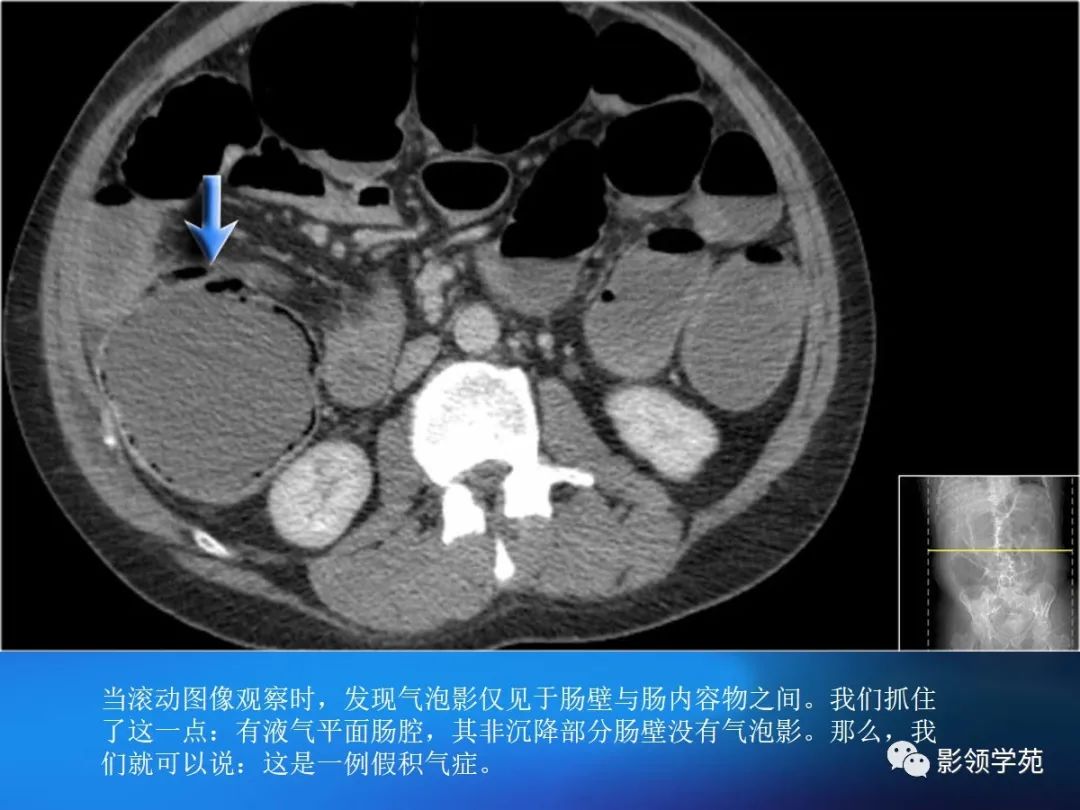

目前尚缺乏统一标准,一般认为,排除肠管充盈不佳或肠壁收缩时导致的假象后,当肠壁大于3mm是即考虑增厚。